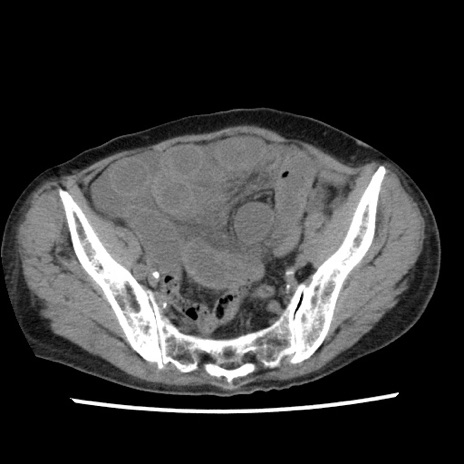

冠状断像

【症例】80歳代女性

【主訴】腹痛

【現病歴】8時間前から腹痛あり来院。

【既往歴】糖尿病、脂質異常症、子宮体癌にて子宮全摘術

【身体所見】意識清明・会話良好だが腹痛で苦悶様、全腹部にわたって反跳痛と圧痛あり

【データ】WBC 13600、CRP 0.14、LDH 224、CK 90